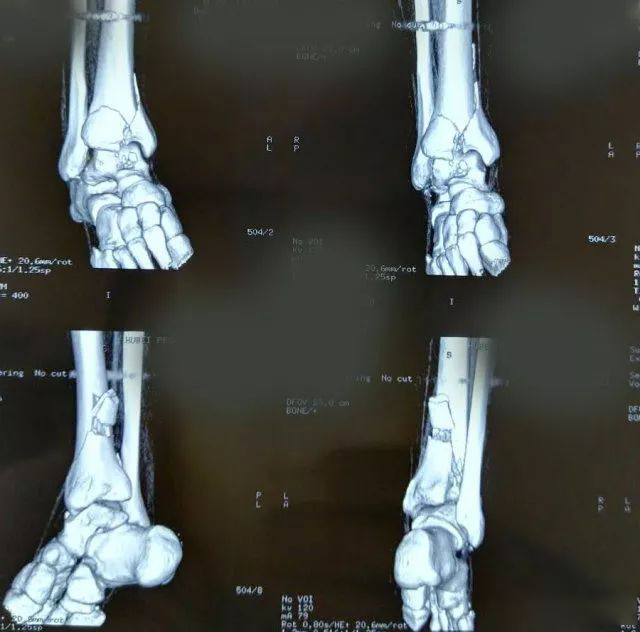

一起来看一个病例:男,20岁,摔倒右踝3天,体格检查示右小腿下段肿胀压痛,活动受限,运动感觉可,诊断为右侧 Pilon骨折。X片及CT三维图如下,欢迎投票并在评论区附上理由。